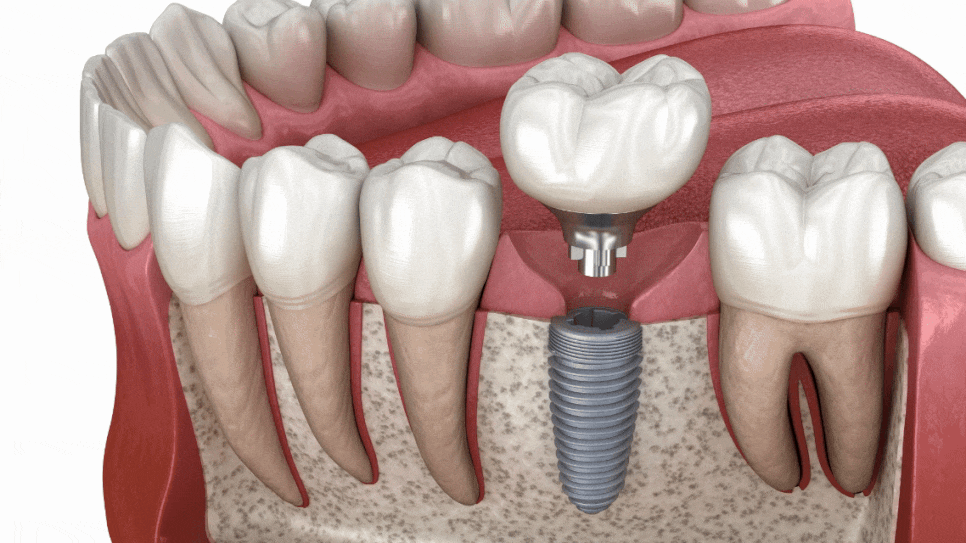

임플란트의 차이는

‘처음 설계’에서 시작됩니다.

임플란트를 단순히 나사를

심는 방식이라고 생각하시기 쉬워요.

하지만 실제로는 그렇지 않습니다.

뼈 상태→

위치 각도→

저작하는 힘→

보철 연결

이 모든 과정이 이어져야 하죠.